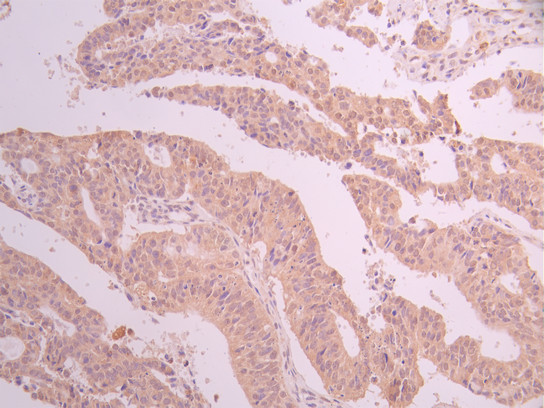

• IHC image of CSB-RA018403MA1HU diluted at 1:50 and staining in paraffin-embedded human ovarian cancer performed on a Leica BondTM system. After dewaxing and hydration, antigen retrieval was mediated by high pressure in a citrate buffer (pH 6.0). Section was blocked with 10% normal goat serum 30min at RT. Then primary antibody (1% BSA) was incubated at 4°C overnight. The primary is detected by a Anti-Human lgG, Fcy Fragment Specific labeled by HRP and visualized using 0.05% DAB.